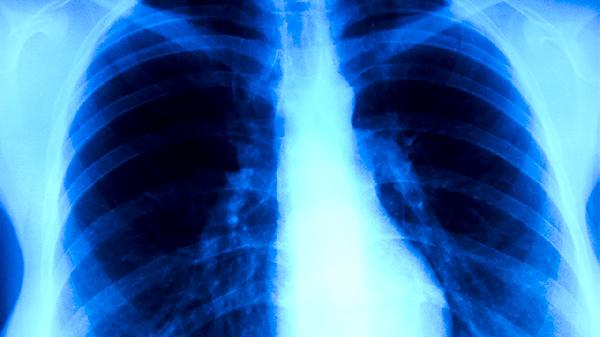

耐多药肺结核患者治疗周期通常需要18-24个月,远超过普通肺结核的6个月标准疗程。由于药物敏感性降低,治疗方案需选用二线抗结核药物,这些药物价格昂贵且副作用更明显。治疗过程中可能出现肝功能损害、听力下降、肾功能异常等药物不良反应,部分患者因无法耐受而中断治疗。耐多药结核分枝杆菌在社区中的传播风险持续存在,患者排菌期延长导致传染性持续时间增加。疾病进展可能引发肺组织广泛破坏,形成肺空洞、支气管扩张等不可逆病变,严重者可发展为慢性肺源性心脏病。

耐多药肺结核患者死亡风险是普通肺结核患者的3倍以上,合并HIV感染时死亡率进一步升高。治疗费用可达普通肺结核的100倍,长期用药和住院给家庭带来沉重经济压力。耐药菌株可通过飞沫传播给密切接触者,造成家庭和社区传播。疾病导致的劳动能力丧失可能持续数月甚至永久性残疾,严重影响患者生活质量和社会功能。儿童患者可能出现生长发育迟缓、营养不良等远期健康问题。